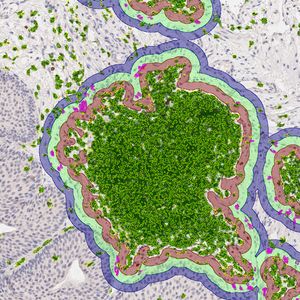

AUG 10, 2024Health & MedicineLiver disease is a complex and multifaceted health concern that affects millions of people worldwide. While lifestyle fa ...